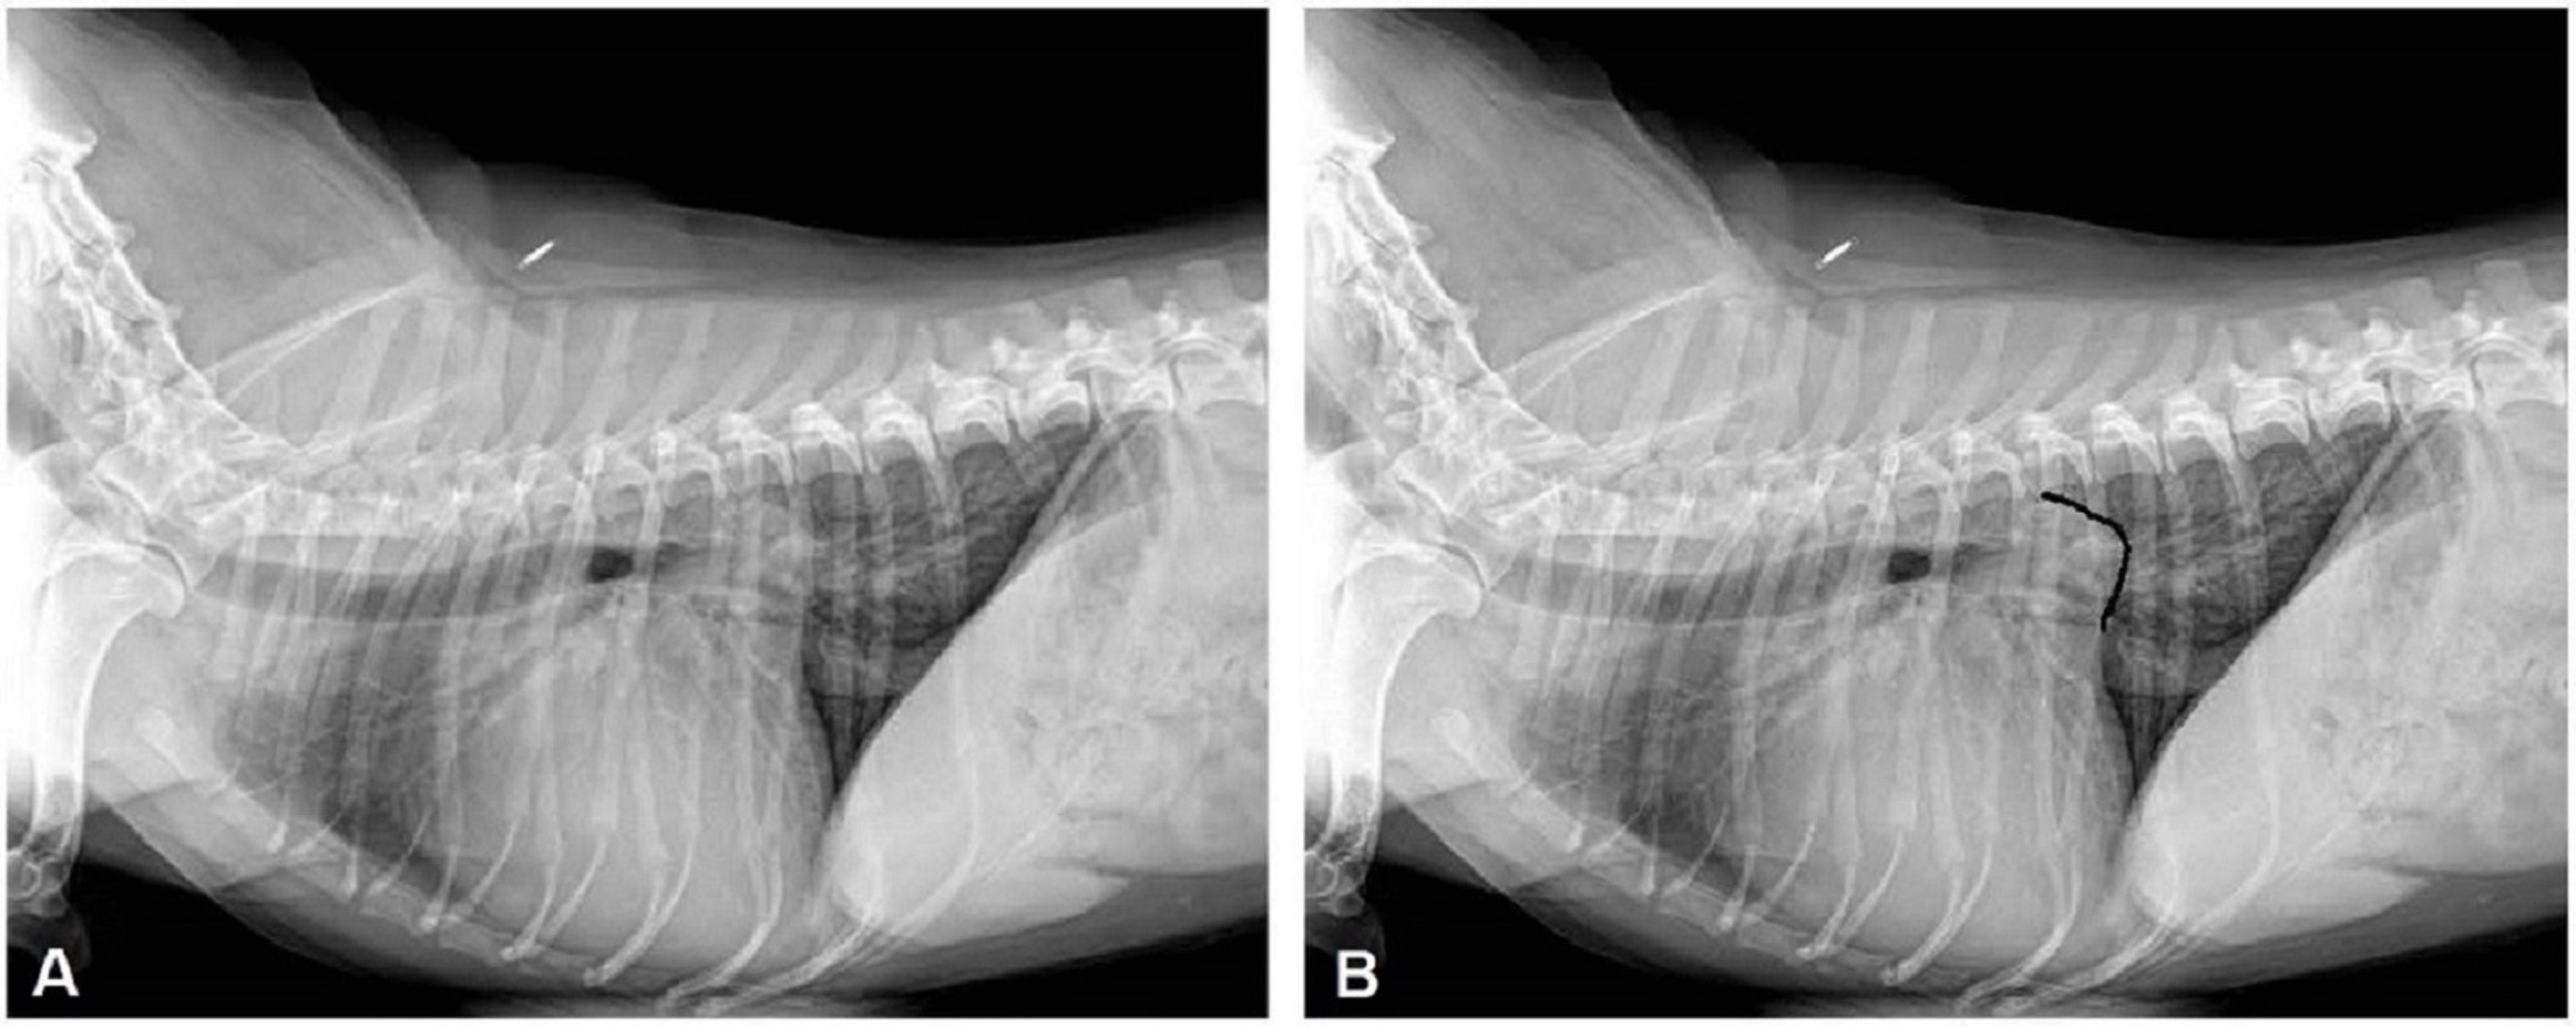

Congestive heart failure, dog, radiograph

Lateral radiograph of a dog with cardiogenic pulmonary edema due to severe mitral regurgitation. Note the large body of the left atrium (outlined in part B) almost touching the spine.

Courtesy of Dr. Mark D. Kittleson.